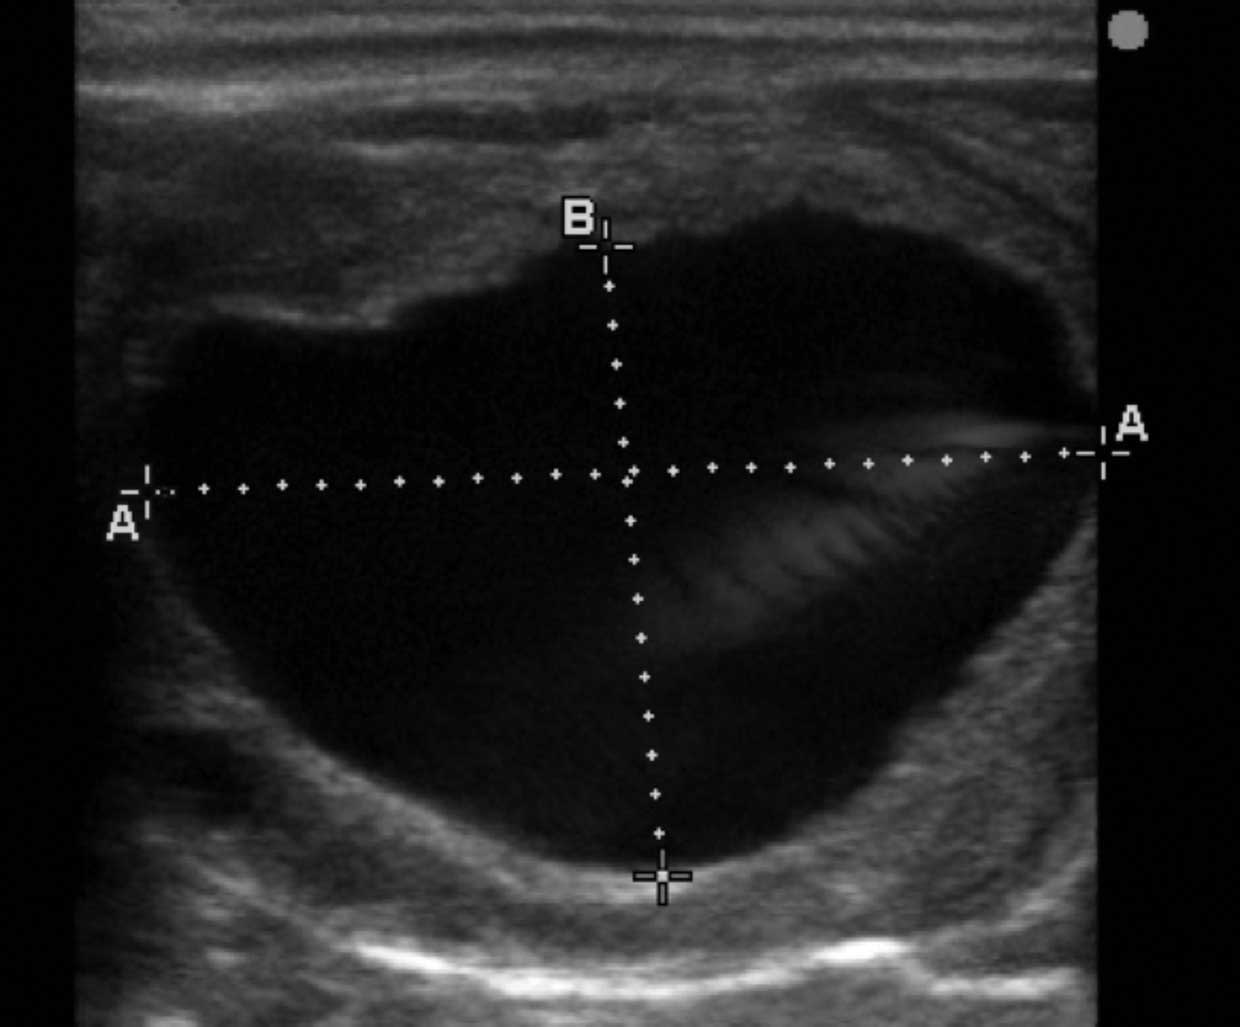

Transrectal palpation of a mare in oestrus will reveal a soft relaxed cervix, a heavy oedematous uterus, and the presence of large and softening ovarian follicles. Ultrasound examination will reveal a characteristic oedema pattern of the uterus in response to oestrogen secretion and large fluid‑filled hypoechoic follicles.

In contrast, mares in dioestrus will have a tight cervix and a toned uterus on palpation with a homogenous pattern, and no evidence of uterine oedema on ultrasound examination. A corpus haemorrhagicum or CL will be present on ovarian ultrasound.

Mares may display discomfort on ovarian palpation following a recent ovulation and collapse of the follicular wall can often be detected. Ultrasound examination will reveal lutenisation of the previous dominant follicle and the presence of either a blood/fibrin filled corpus haemorrhagicum with an echogenic rim and hypoechoic centre or a more homogenous echogenic CL.